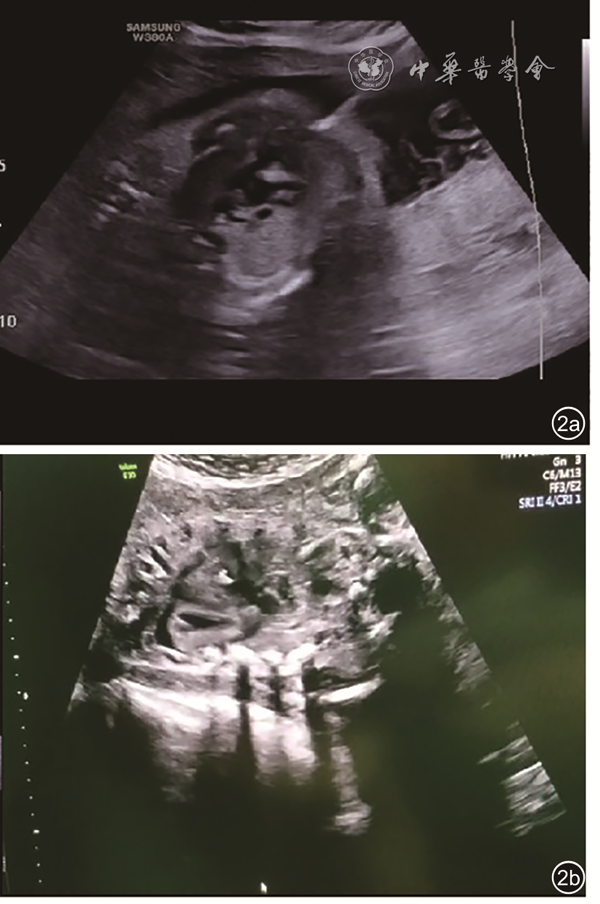

From July 2018 to May 2019, 12 fetuses were diagnosed with pulmonary atresia with intact ventricular septum (PA/IVS) with right heart dysplasia and treated at the Women and Children's Hospital, Qingdao University. The median gestational age was 27 (26-28) weeks. All fetuses underwent FCI under the guidance of echocardiography. Our experience with the application of perioperative echocardiography in FCI was then summarized.

All fetuses in this study underwent FCI successfully, with an average operation time of 5.3±1.11 min. Bradycardia occurred immediately after FCI in 5 fetuses, which needed to be treated with epinephrine or atropine in the right atrium. A small amount of pericardial hematocele can be absorbed by the fetus in the early stage after FCI. One mother each chose to terminate pregnancy due to heart failure and due to right ventricular dependent coronary circulation. Finally, 10 fetuses were born alive, and most fetuses needed intervention again after birth, and achieved biventricular circulation.

Echocardiography plays an important role in preoperative indication evaluation, intraoperative guidance, and postoperative observation of FCI. Standardized operation is the key to ensuring the success of FCI.